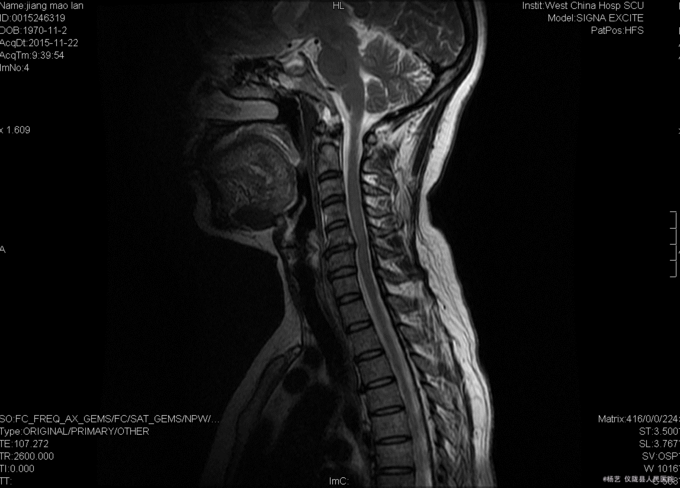

患者蒋茂兰,女,45岁0月,因“头晕伴视物旋转10+月,加重1+月。”入院 10+月前患者无明显诱因出现头晕、头昏;视物旋转,偶伴有呕吐,呕吐为胃内容物;间断发作,发作时持续时间不等,休息后明显缓解。无活动障碍;无肢体麻木、乏力;无行走不稳;无发热、头痛等,1+月前患者上述症状加重,患者于当地医院就诊,治疗未见明显好转。颈椎MRI示:颈5/6椎间盘突出。现患者为求进一步诊治就诊于我院,门诊以“C5/6椎间盘突出症伴脊髓神经不全损害”收入我科。

查体:T:36.9oC,P:78次/分,R:19次/分,BP:109/72mmHg。神志清楚,无病容,皮肤巩膜无黄染,全身浅表淋巴结未见肿大。。颈静脉正常。心界正常,心律齐,各瓣膜区未闻及杂音。胸廓未见异常,双肺叩诊呈清音,双肺呼吸音清,未闻及干湿啰音及胸膜摩擦音。腹部外形正常,全腹柔软,无压痛及反跳痛,腹部未触及包块,肝脏肋下未触及,脾脏肋下未触及,双肾未触及。双下肢无水肿。 专科查体:视:脊柱外观无畸形,活动无异常,无皮肤破溃及窦道形成。触:椎体棘上、椎旁肌无压痛、叩痛,四肢感觉无明显减退,远端血运未见异常。动量:颈部屈伸、左右侧偏活动无明显受限,双上肢耸肩、屈伸肘关节、屈伸腕肌力5级,双手握力5级,双下肢伸髋、屈髋、外展、内收、伸膝、屈膝肌力5级,双足趾背伸肌力5级。双侧肱二、三头肌肌腱反射、膝腱反射、跟腱反射正常引出。双侧Hoffmann氏征阳性,Babinski征阴性,踝阵挛阴性,髌阵挛阴性。 辅助检查:外院MRI示:颈椎退行性变,颈5/6椎间盘突出。垂体区:空泡蝶鞍?

综上初步诊断:1、颈5-6椎间盘突出症伴脊髓神经不全损害;2、白癜风 经前路颈5/6椎间盘切除、椎管及椎间孔减压、椎间融合器植骨融合内固定术。 手术发现:  颈5/6椎间隙变窄,椎间盘髓核干涩,无光泽。颈5/6椎间隙后份少量骨赘生成,椎间盘向后方突出,压迫硬脊膜。术中夹出数块突入椎管内的椎间盘髓核组织及增生骨赘。充分减压后,可见硬脊膜恢复膨隆,双侧神经根松弛,术中未见脑脊液漏。